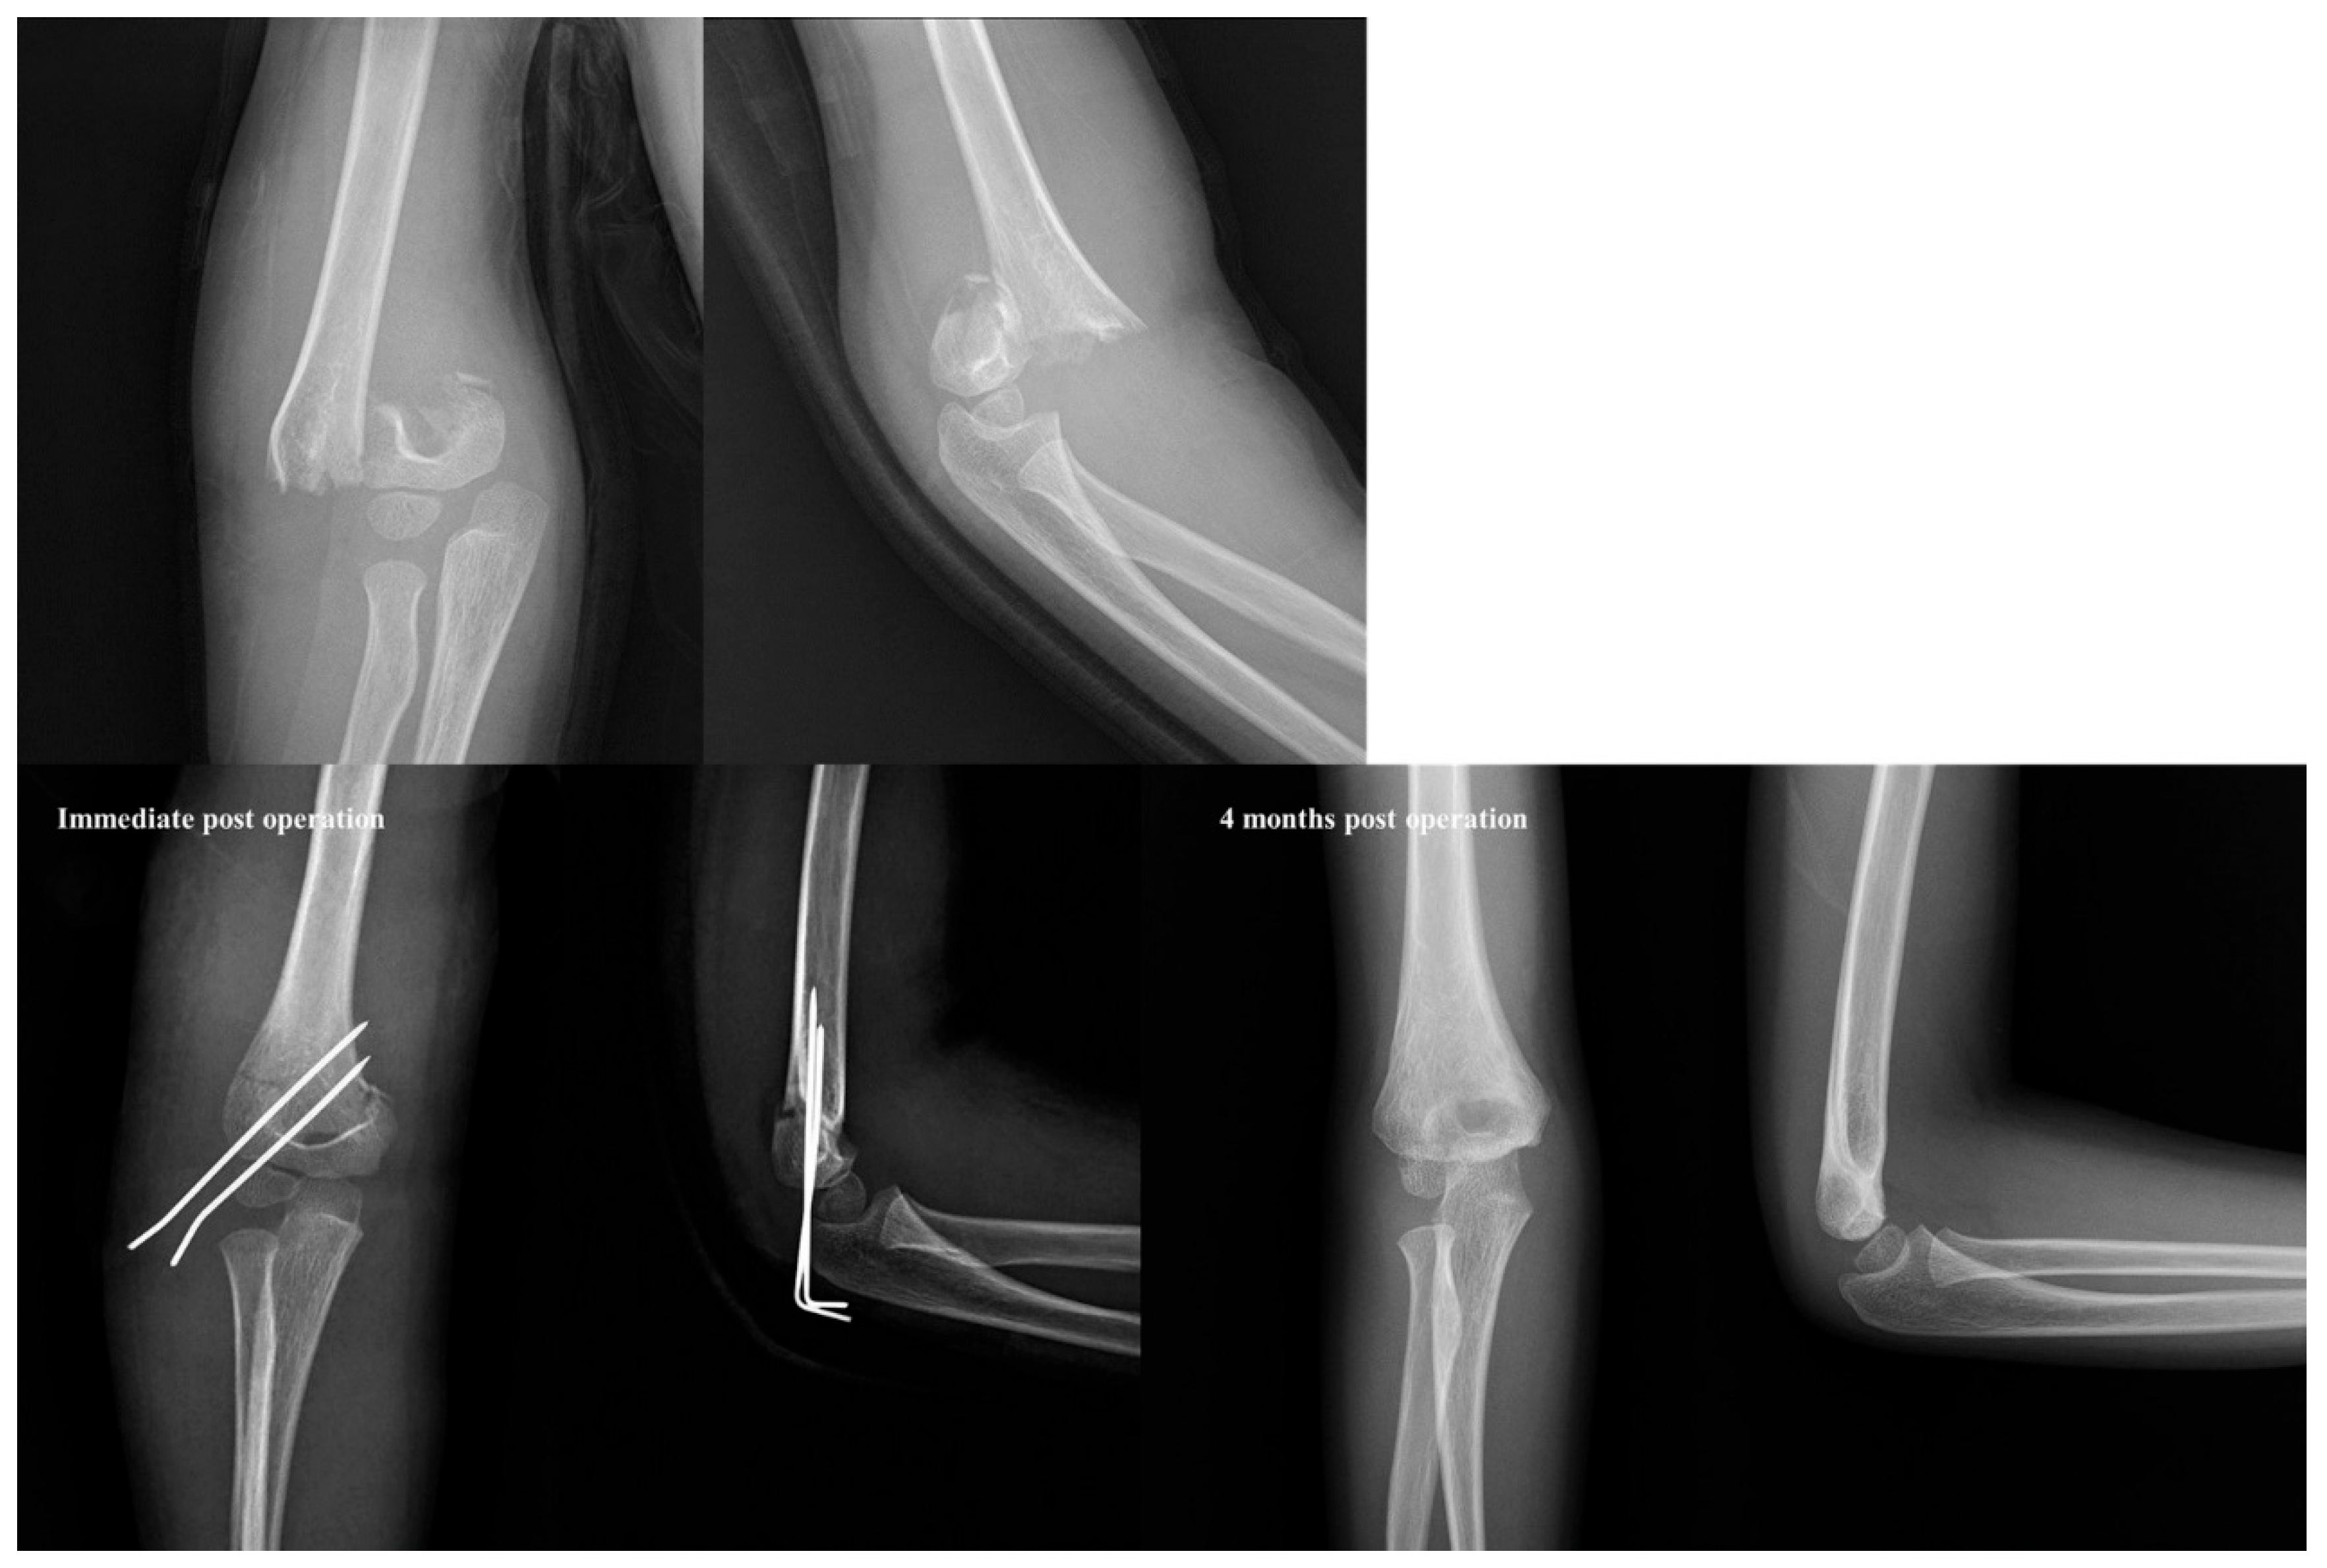

Figure 4. Example of a low transverse fracture type in a 6-year-old boy with a Gartland type III supracondylar fracture. Despite being a Gartland type III fracture, the internal rotational stress test was negative, even with only two lateral pins fixation. Furthermore, there was no loss of reduction in the radiographs taken 4 months post-operation.

Figure 6. Despite being a Gartland type III fracture, the patient was treated with only two lateral pins and there was no loss of reduction at 2 months post-operation. This configuration increased the angle between the direction of the fracture line and the direction of the pins inserted laterally, resulting in strong fixation.